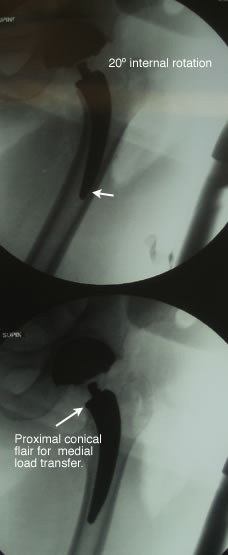

Femoral rotation can be misleading on stem orientation. However with this curved tissue and neck sparing stem design distal stem position is not necessarily a negative finding as compared to conventional cemented or conventional cementless length stems. We have found that with this particular stem style that slight varus, neutral or valgus distal stem position has had no difference in clinical and radiographic outcomes at two years.

The distal stem for this design has less function than conventional cementless stems that rely on stem/bone contact for reduction of torsional loads.

The distal stem has an angled relief to reduce chances of end stem contact. |

As seen here in these two proximal x-ray comparisons the bottom is a view of the curved neck sparing design size 2 rasp with good proximal fit and excellent maintenance of both the medial and lateral portions of the neck. This was then converted to a short taper style stem and required more removal of both vertical and lateral neck, resulting in a lager stem (size 5) being needed for good implant/bone stability.

This case confirms previous case studies that on average a size two curved neck sparing stem results in a size 5-6 short tapered style stem requiring more vertical medial and lateral neck removal.

It also re-confirms that no special tables or instruments are needed to insert a small curved neck sparing stem in a single incision anterior approach. |